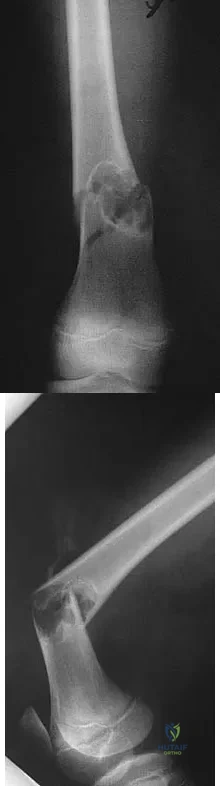

A 10-year-old child reports acute leg pain after wrestling with his brother. AP and lateral radiographs are shown in Figures 21a and 21b. What is the best course of action?

Explanation